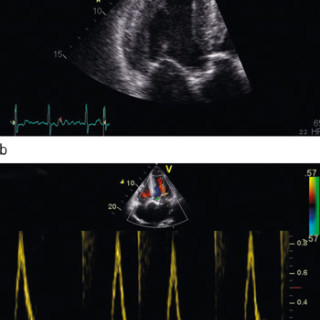

Educational case report